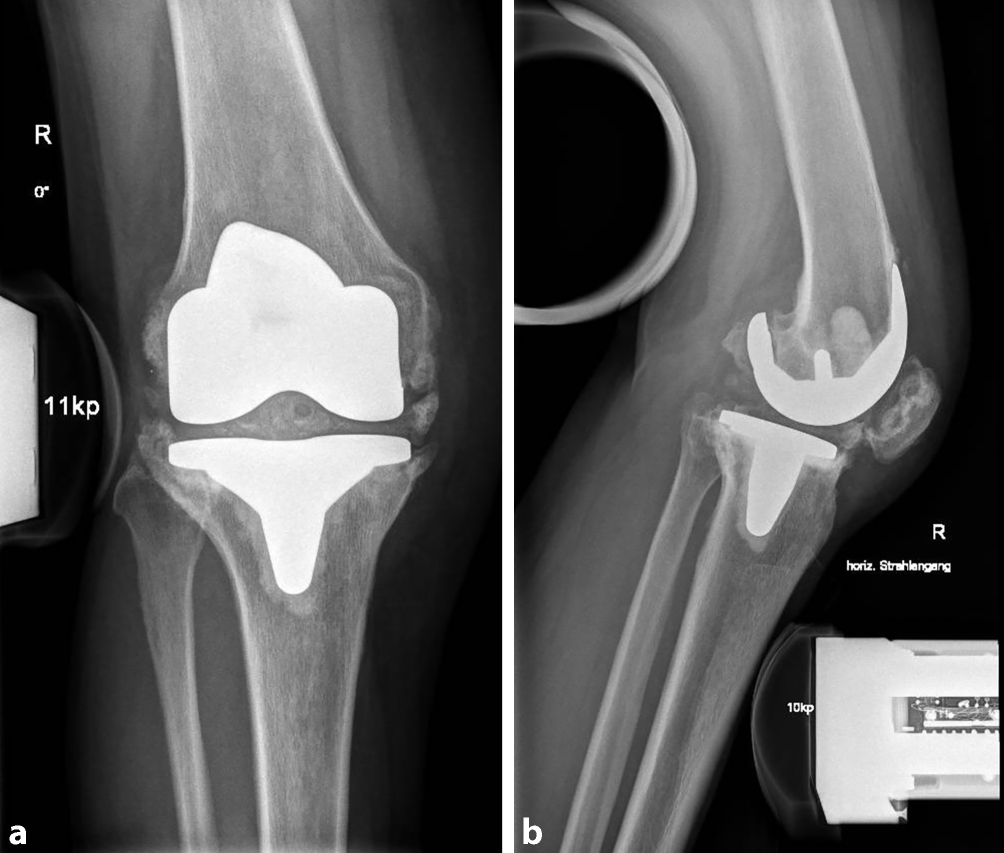

Stress-Röntgenaufnahmen, eine Aufnahme nach Kanekasu ([48]; Abb. 2) oder eine fluoroskopische Untersuchung des Kniegelenks stellen eine sinnvolle Ergänzung zur konventionellen Röntgendiagnostik dar, insbesondere bei Verdacht auf eine Instabilität. Stress-Röntgenaufnahmen werden immer beidseits und in folgenden Positionen durchgeführt: anterior-posteriorer Strahlengang mit Varus-Valgus-Stress in 15° Flexion, anterior-posteriorer Strahlengang mit Varus-Valgus-Stress in voller Extension, lateraler Strahlengang mit anterior-posteriorem Stress in 15° Flexion, lateraler Strahlengang mit anterior-posteriorem Stress in 90° Flexion (Abb. 3; [49]).

Abb. 3

Heterotope Ossifikation, Knie rechts. Stress-Röntgenaufnahmen in anterior-posteriorem (a) und lateralem (b) Strahlengang